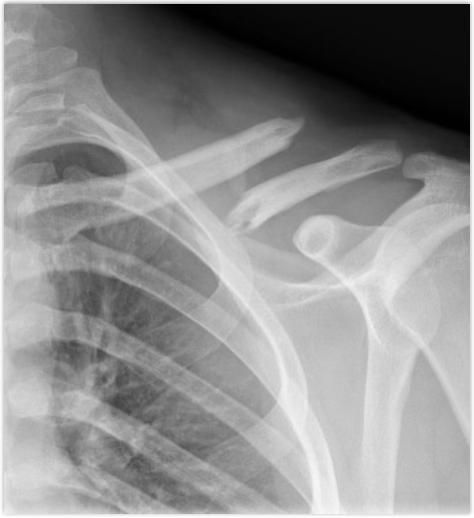

how does a clavicle fracture occur?

falling on outstretched hand or a direct hit

symptoms of clavicle fracture

pain, deformity, lack of ROM, swelling, and a snap

treatment of clavicle fracture

Check for neurovascular injuries

If in alignment, they get a figure 8 brace or sling and eventually PT

If not in alignment, they get new hardware, sling, and PT